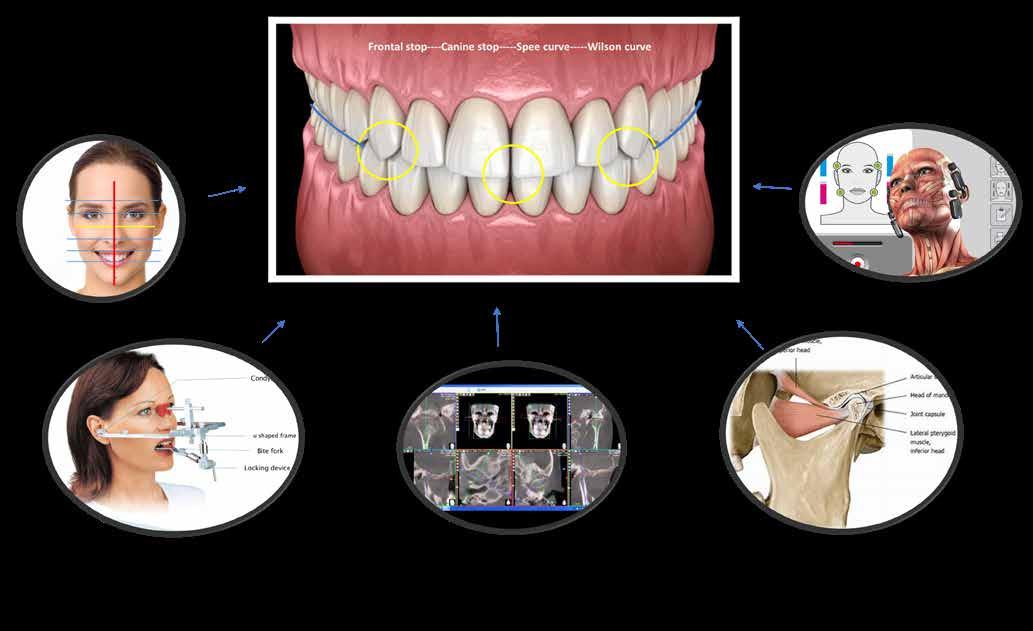

Dr. Csillag MáriaA komplex esztétikai munkák készítésekor óhatatlanul funkcionális megoldásra is váró esetekkel találkozunk, amelyek nagy többségében temporomandibuláris ízületi fájdalmakkal járnak, és diszfunkciókkal járó kórképeket is kezelnünk kell. A fogak érintkezésének kialakításakor így nem elegendő az esztétikai irányelveket alkalmaznunk, hanem egy komplex szemléletrendszerre, ezen belül az okklúzióról tanult ismereteinkre is szükségünk van.

Minden rendszer, probléma akkor lesz átlátható és megfejthető, ha több szemszögből is vizsgáljuk (1. kép). A képen ugyanaz a formarendszer látható más-más perspektívából szemlélve: egy kör, melynek középpontján egy egyenes halad át. Az egyik oldalról keresztként látható, a másik oldalról egy kör, közepében pont figyelhető meg. A helyes fogérintkezések kialakításakor is célszerű több szempont szerint megvizsgálni a helyzetet, és igénybe venni a megoldásokhoz különböző diagnosztikai, illetve megvalósítási módszert is. Így segítségünkre lehet az egyedi középvonal-rendszerek is-

merete, az arcredő diagnosztika, az izomdiagnosztika (Smylist besorolás), a TMI-ről alkotott tudásunk, a CT/MRI vizsgálatok, az egyedi artikulátorok és a miotómok alkalmazása, esetlegesen arcívek használata, továbbá a digitális tervezés is (2. kép). A Smylist Módszer például összetett szemlélettel közelíti meg az okklúzió kérdését. A maxilla fogainak állását, elhelyezkedését az arckoponyából számolva tervezi meg, a mandibula fogainak érintkezését pedig az izomdeprogramálással meghatározva hozzárendeli a már kialakított maxilláris fogakhoz. Az okklúziót egyetlen helyes pozícióban tudja elképzelni, ahol minden izom feszülésmentes. Minden egyes paraméternek, dőlésnek jelentősége van mind az esztétikai, mind pedig a funkcionális téren. A láthatóan nem esztétikus megjelenés biztosan rejt magában funkcionális problémát is. Például egy kijjebb álló szemfog esztétikailag sem ad megfelelő látványt, de laterális stop és szemfogvezetés hiánya miatt funkcionális gondot is fog okozni. A rövidre tervezett

Sajnos a megoldásra váró komplex eseteink többségében azonban aszimmetrikus izomműködéssel állunk szemben, amelyben egy dinamikusan változó fogérintkezést figyelhetünk meg egy-egy időpillanatban. Így az adott okklúzió a legtöbb esetben illúzió, hiszen folyamatosan változik, azonban a fogmigrációs folyamat lassú dinamikája miatt ez a változás csak évek alatt érzékelhető (5. kép). Így szigorúan véve, minden fogazatot érintő beavatkozás – amennyiben nincsen megfelelő izomszimmetria – csupán egy instabil rendszerben való építkezési kísérlet, amelynek eredménye logikai alapon is a 24 gomphózis ízületi komplexum adott elemeinek – egy-

egy fog vagy gyökér körüli terület, vagyis ízület – biztos túlterhelése lesz. (Ennek mintázata egyébként az izomműködés aszimmetriájából, az állkapocs rotációjából adódóan teljesen típusos a Smylist besorolás szerint). A fogorvos feladata tehát minden egyes komplex és nem komplex beavatkozás esetén az lenne, hogy ezt az adott izomszimmetriát a megfelelő okklúzális viszonyok kialakításának biztosítása érdekében megteremtse, illetve megtartsa. A Smylist rendszerben az állkapocs nyugalmi helyzetében létrejövő fogérintkezést, okklúziót BOP-nek (Balanced Occlusal Position) nevezzük. Minden más izomspazmussal járó állkapocs helyzetben létrejövő fogérintkezést FOP (Forced Occlusal Position), azaz forszírozott, erőltetett állkapocs pozíciónak hívjuk. Ennek az izomaszimmetriának a jelei rögtön mutatkoznak nem csak a rágóizomzatban, hanem a mimikai izomzatban is, izomelváltozásokat okozva az arcon. Ezek az izomeltérések jellemzőek lehetnek egy-egy izomcsoportra, illetve az arc egészére is típusos képet adnak: masseterhipertófia, mentális izom megnagyobbodása, zygomatikusz izom aszimmetrikus ellapulása (6. a-b-c kép) Minden BOP-ben, azaz harmonikus, izomszimmetriában kialakított fogérintkezésben készülő komplex esztétikai beavatkozás, fogszabályozási terápia, implantprotetikai megoldás stabil, problémamentes eredményt ad, hiszen aszimmetrikus erők nem fognak fellépni a pótlások átadása után. Azonban, ha a munkák FOP-ben készülnek, akkor számítani kell a héjak, koronák lepattanására, az implantációs pótlások esetleges kimozdulására, a parodontális esztétikai műtétek siker-rátájának csökkenésére, a fogszabályzó kezelések eredményének kollapszusára. Ezekben a helyzetekben a fogakat jelentős aszimmetrikus izomerő éri. Ahhoz, hogy ez ne történjen meg, az izmokat deprogramálni kell, amelyre többféle módszer is létezik. Az izomdeprogrammálást követően egy olyan állkapocshelyzet jön létre, amely viszonyításként megmutatja, hogy a fogaknak hol kellene érintkezniük (6. kép). Ebben a relációban szükséges kialakítani a helyes fogérintkezéseket, a frontfogak, szemfogak közötti stopokat, a Spee- és a Wilson görbéket, a hármas egységeket, továbbá a fogak ötpontos érintkezéseit (7. a-b kép). Fontos ezen kívül a megfelelő overbite és overjet kialakítása, a fogexpozíció mértéke, és a fogak, ajkak viszonyának helyes kialakítása is.